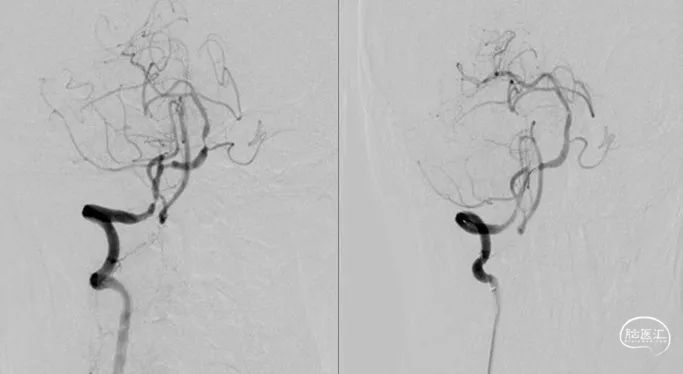

6F导引导管进入V2后,Synchro-14 (200cm)微导丝配合Gateway 2.5mm×9mm球囊先后进行基底动脉、椎动脉V4段狭窄扩张。

撤出球囊后,Synchro-14(200cm)微导丝配合XT-27至基底动脉远端,从远至近分别置入Neuroform EZ 3mm×15mm及Neuroform EZ 3.5mm×20mm支架。

1.串联型血管狭窄是临床中常见的类型,起始处狭窄较重时可先用球囊扩张解决通路上行问题,再根据颅内串联病变情况对进行灵活处理。起始处释放支架前,需确认颅内段血流通畅,避免撤出通路系统后,出现颅内血管需要再次处理,但导引导管无法通过开口支架的情况。

2.Gateway球囊具有通过迂曲病变,到位能力强、扩张时充盈平稳等特点,为颅内血管的治疗提供安全、有效保障。

3.Neuroform EZ支架经导管内释放,容易通过严重迂曲的病变,特别在治疗串联病变时比球扩支架有明显优势。支架采用开环设计,在动脉粥样硬化严重病变处贴壁良好,同时具有较强的径向支撑力,血栓发生率低。但不足的是,如需要支架内球囊扩张时,上行球囊可能会被支架网丝阻拦,造成手术失败。